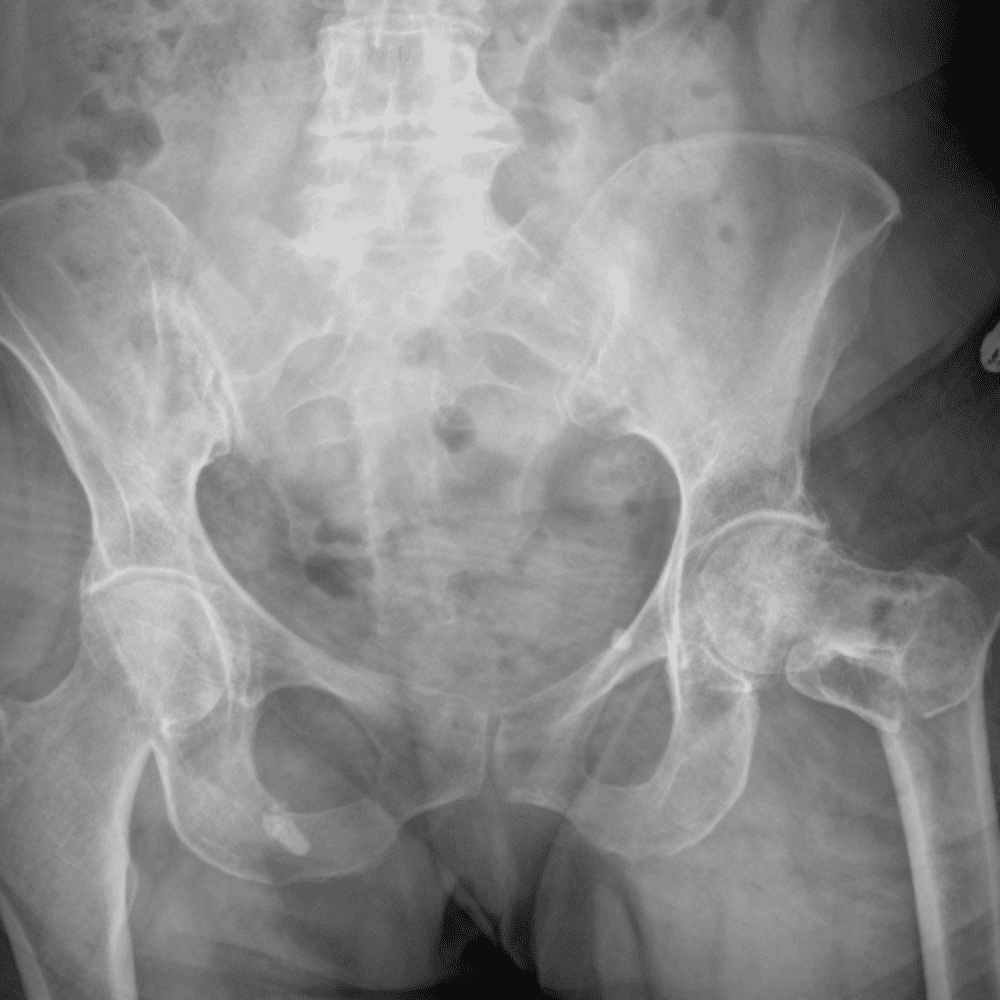

通过包含微妙或困难的病例和一些正常病例来模拟值班。

30 病例